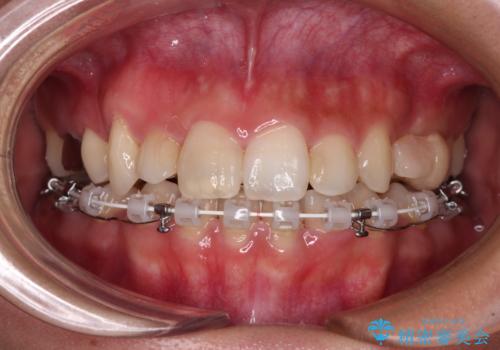

気になる八重歯 目立ちにくいハーフリンガルでの抜歯矯正

- 八重歯や前歯のデコボコを気にして来院された患者様です。

目立たない装置を希望されたので、上顎が裏側装置のハーフリンガルを選択し、上下左右の小臼歯(計4歯)を抜歯して矯正治療を行うこととしました。

補助装置を併用することで、八重歯を速やかに改善し、治療期間の短縮を図ることとしました。

裏側装置での矯正治療は、上顎前歯の正中のズレをまっすぐに改善することが難しいのですが、きれいに整えることができました。

補助装置を用いて抜歯したスペースを速やかに閉じたことで、短期間での治療となりました。